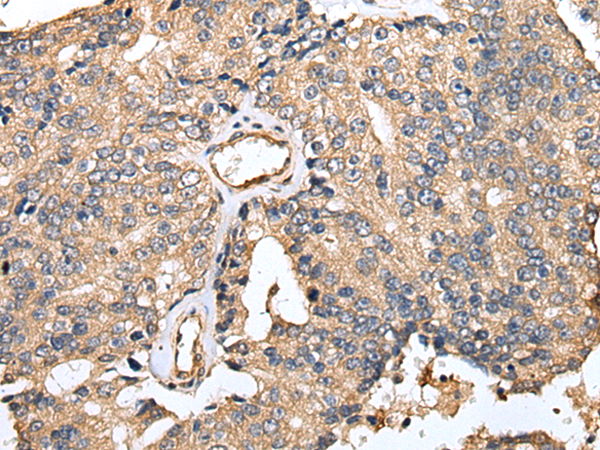

分类: 科研抗体货号: P02116别名: MBP2; MBPH应用: IHC反应种属: Human